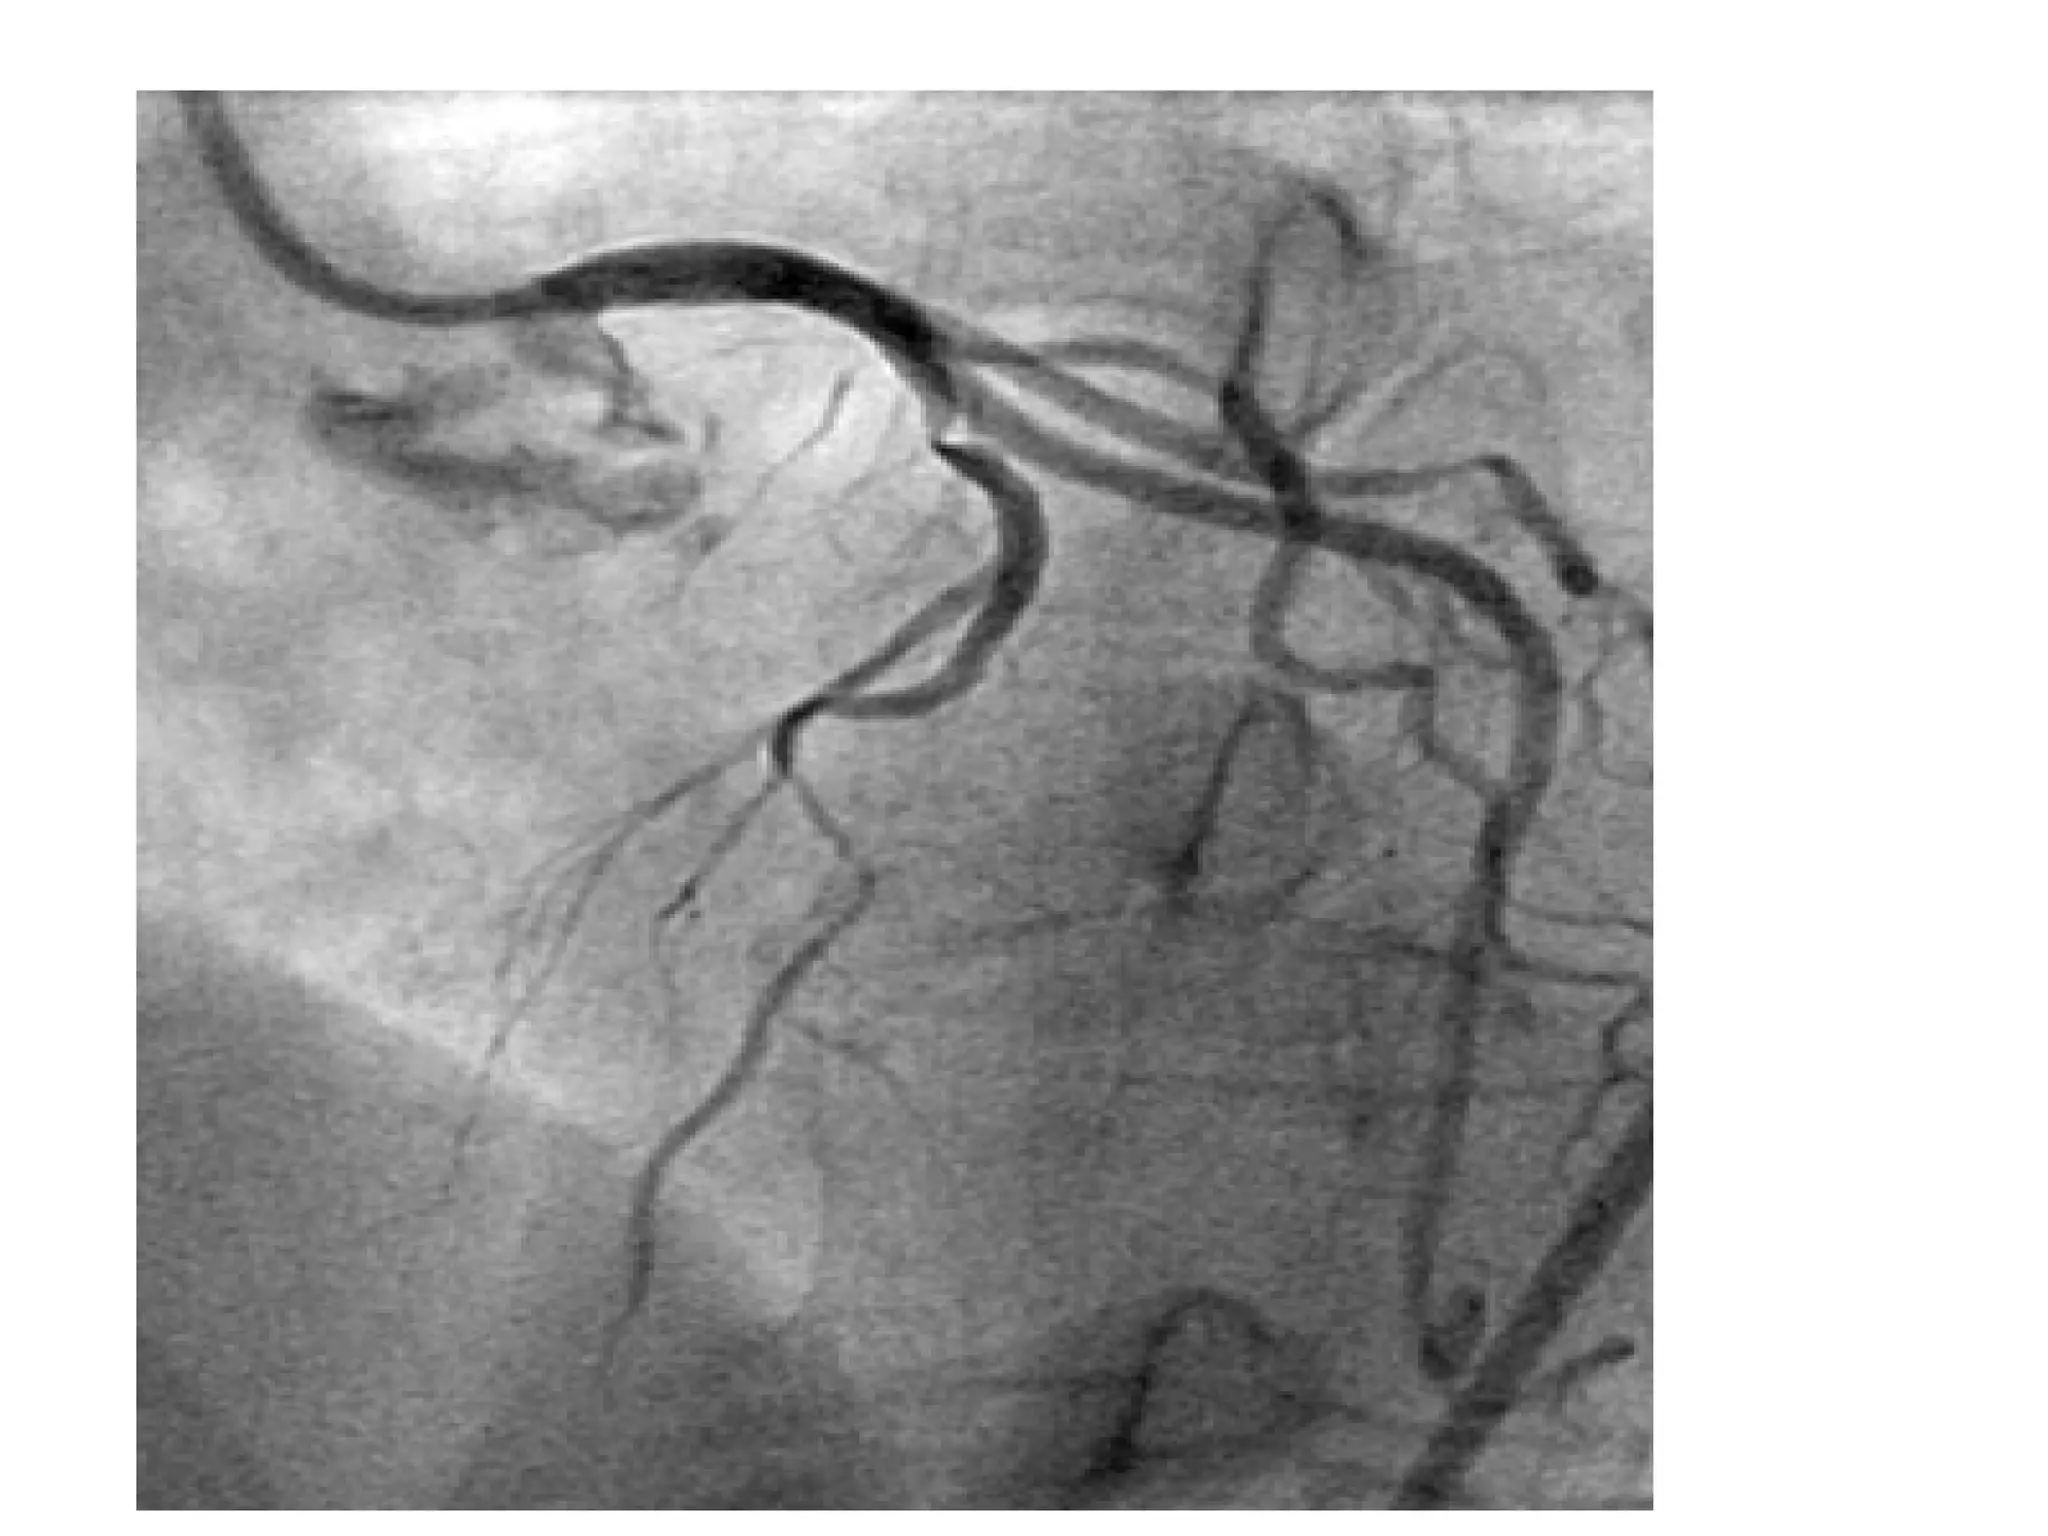

A 43-year-old man presented with chest pain and was diagnosed with an acute inferior ST elevation myocardial infarction with evidence of right coronary artery occlusion but no right ventricular involvement; he underwent primary percutaneous coronary intervention of the mid right coronary artery, which had a clot. The same patient had a complex lesion in the left anterior descending artery and its diagonals requiring staged percutaneous coronary intervention. A 55-year-old woman with diabetes and chest pain was found to have severe reversible ischemia in the territories of the left anterior descending artery and right coronary artery on nuclear stress testing, with normal circumflex artery area; coronary angiography revealed a critical proximal lesion in the left anterior descending artery.